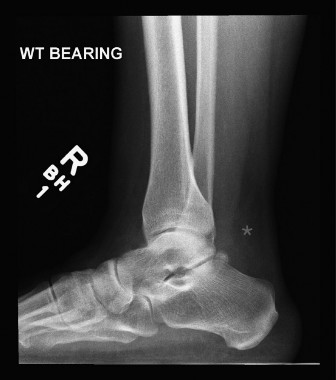

A 52-year-old male presents to your office reporting increased medial and lateral hindfoot pain for the past …